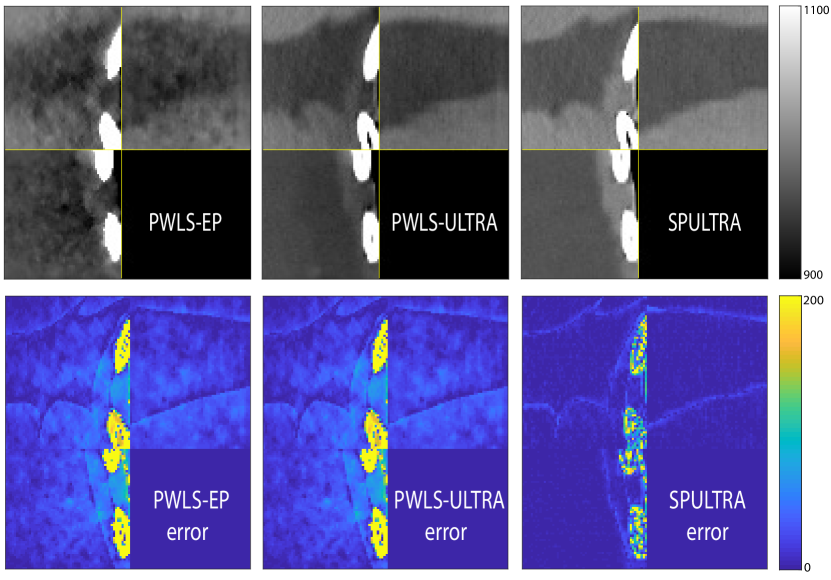

Fig. 4 shows the reconstructed images and the corresponding error images for PWLS-EP, PWLS-ULTRA, and SPULTRA, at and . Compared to the PWLS-EP result, both PWLS-ULTRA and SPULTRA achieved significant improvements in image quality in terms of sharper reconstructions of anatomical structures such as bones and soft tissues, and suppressing the noise. However, the PWLS-ULTRA method introduces bias in the reconstructions, which leads to larger reconstruction errors compared to the proposed SPULTRA method. In Fig. 4, we marked three 3D ROIs in the axial plane, i.e., ROI 1, ROI 2, and ROI 3. Fig. 5 shows the zoom-in images of a 3D plot of ROI 1, and those of ROI 2 and ROI 3 are shown in the supplement. We also plot the evolution of RMSE through the axial slices of the three 3D ROIs in Fig. 6. The figures demonstrate that SPULTRA clearly outperforms the competing PWLS-EP and PWLS-ULTRA schemes.

The above advantages of SPULTRA can be seen more clearly when observing the image profiles. Fig. 7 plots the image profiles for the three methods together with that of the ground-truth image. Fig. 4 shows the horizontal green solid line and the vertical red dashed line, whose intensities are plotted in Fig. 7. It is obvious that the profiles for SPULTRA are closest to the ground-truth among the three compared methods. The gap between the profiles of the PWLS-based methods and the ground-truth shows the bias caused by the compared PWLS methods.

Fig. 14 and Fig. 15 plot the zoom-ins and the corresponding error images of ROI 2 and ROI 3 for the XCAT phantom simulations in Section V.A, with and , respectively. In Fig. 15, we highlighted a region in the axial slice with small red arrows. We show the zoom-ins of the ground-truth ROI 2 and ROI 3 of the XCAT phantom in Fig. 16. The results show that SPULTRA improves image quality over PWLS-EP and PWLS-ULTRA by reducing bias and improving image edges.